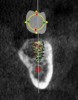

(4.) Digital plan of the virtual implant.

Figure 4

(5.) Digital plan of the virtual implant.

Figure 5